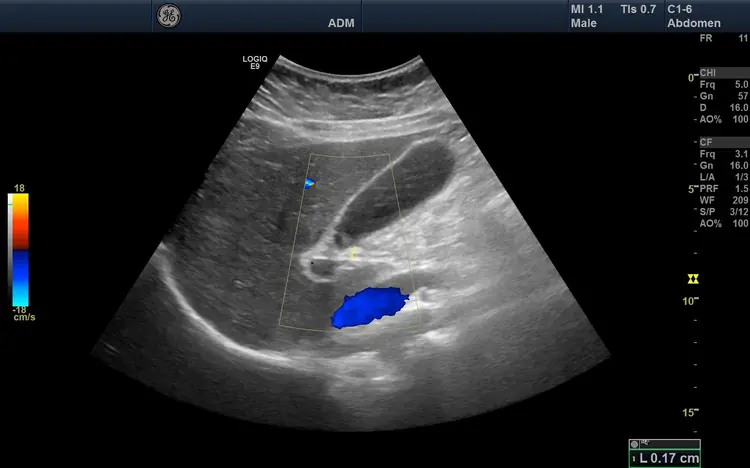

Voir lâaorte avant quâelle ne cĂšde.